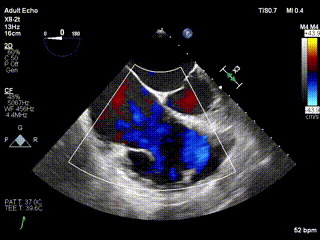

三例患者入院后,葛均波院士團隊周達(dá)新教授、潘文志教授、張源博士、陳莎莎博士及心超室的潘翠珍教授、李偉教授對患者的情況進(jìn)行詳細(xì)評估和討論,最終決定為三例患者選擇LuX-Valve Plus40mm、50mm和50mm型號的瓣膜進(jìn)行手術(shù)治療。手術(shù)后即刻拔除氣管插管,術(shù)后患者三尖瓣反流癥狀得到顯著改善,復(fù)查心超結(jié)果顯示人工三尖瓣瓣膜支架固定穩(wěn)定,瓣葉關(guān)閉形態(tài)未見異常,未見明顯反流。